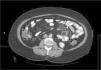

Mujer de 52 años, que tras diagnóstico de síndrome de Sjögren consultó por alteración de las transaminasas y enzimas de colestasis, y AMA positivo con M2 positivos e IgM elevada; se solicitó ecografía abdominal (US) y biopsia hepática y se comenzó tratamiento con ácido ursodesoxicólico a dosis de 14mg/kg/día ante el diagnóstico de colangitis biliar primaria (CBP). La paciente refería evacuaciones pastosas 4-5 veces al día, sin sangre, a lo largo de los últimos 6 meses, con una pérdida de 8kg durante este periodo. La exploración física fue normal. Peso: 65 kg y talla: 167cm. Índice de masa corporal: 23,3. Analíticamente destacaba: alanina aminotransferasa: 68 (0-31) U/l; aspartato aminotransferasa: 113 (0-55) U/l; fosfatasa alcalina: 264 (5-36) U/l; GGT: 341 (35-104) U/l; inmunoglobulinas: IgM: 624mg/dl (40-230); AMA: 1/604; AMA-M2: positivo; antitransglutaminasa: 160 U (0-20). En la US se observaban adenopatías mesentéricas patológicas de aspecto quístico. Los marcadores tumorales fueron normales. El estudio microbiológico fue negativo para virus de la inmunodeficiencia humana y tuberculosis. Se realizó una tomografía axial computarizada (TC) toracoabdominal, observando en el mesenterio la presencia de múltiples adenopatías>1cm, de aspecto quístico redondeado, con área central de baja atenuación (fig. 1). Se realizó una colonoscopia que fue normal y una gastroscopia, observándose un patrón mucoso nodular duodenal de aspecto atrófico con una histología compatible con un estadio Marsh IIIa (figs. 2 y 3). La biopsia hepática fue compatible con una CBP estadio ii.

Los datos clínicos y radiológicos son esenciales en el diagnóstico, siendo la principal herramienta el TC2. El hallazgo inicial por TC es la presencia de múltiples adenopatías localizadas exclusivamente en el meso yeyuno-ileal, de tamaño variable (2-7cm) y con áreas centrales de baja atenuación (densidad en torno a 30-40 UH o inferior) producida por la presencia de líquido y/o grasa.